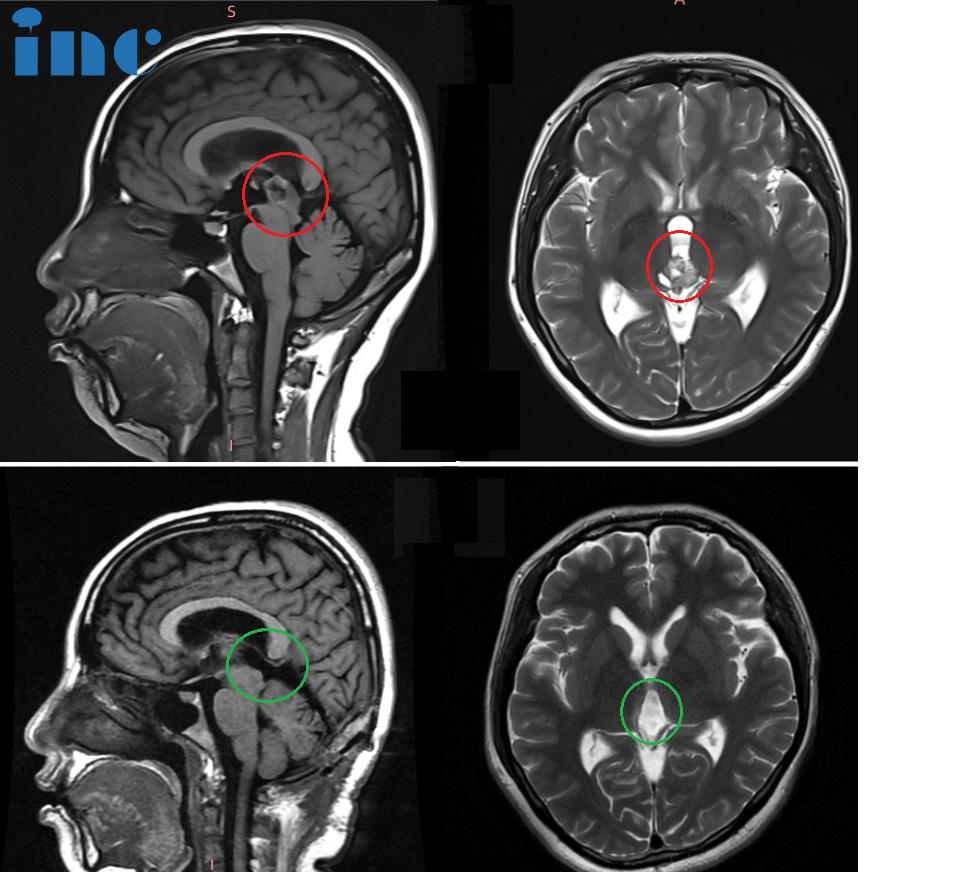

今年,截至目前巴教授指导手术的8个病例的术前磁共振资料,肿瘤位于脑干、脑室、桥臂、颞叶、小脑等疑难位置。

▼部分苏州独墅湖医院巴教授成人手术患者术前影像,接受手术的多名患者肿瘤分别位于脑干、脊髓及丘脑、基底节、桥臂、松果体、鞍区、功能区、CPA桥小脑脚区等疑难位置。